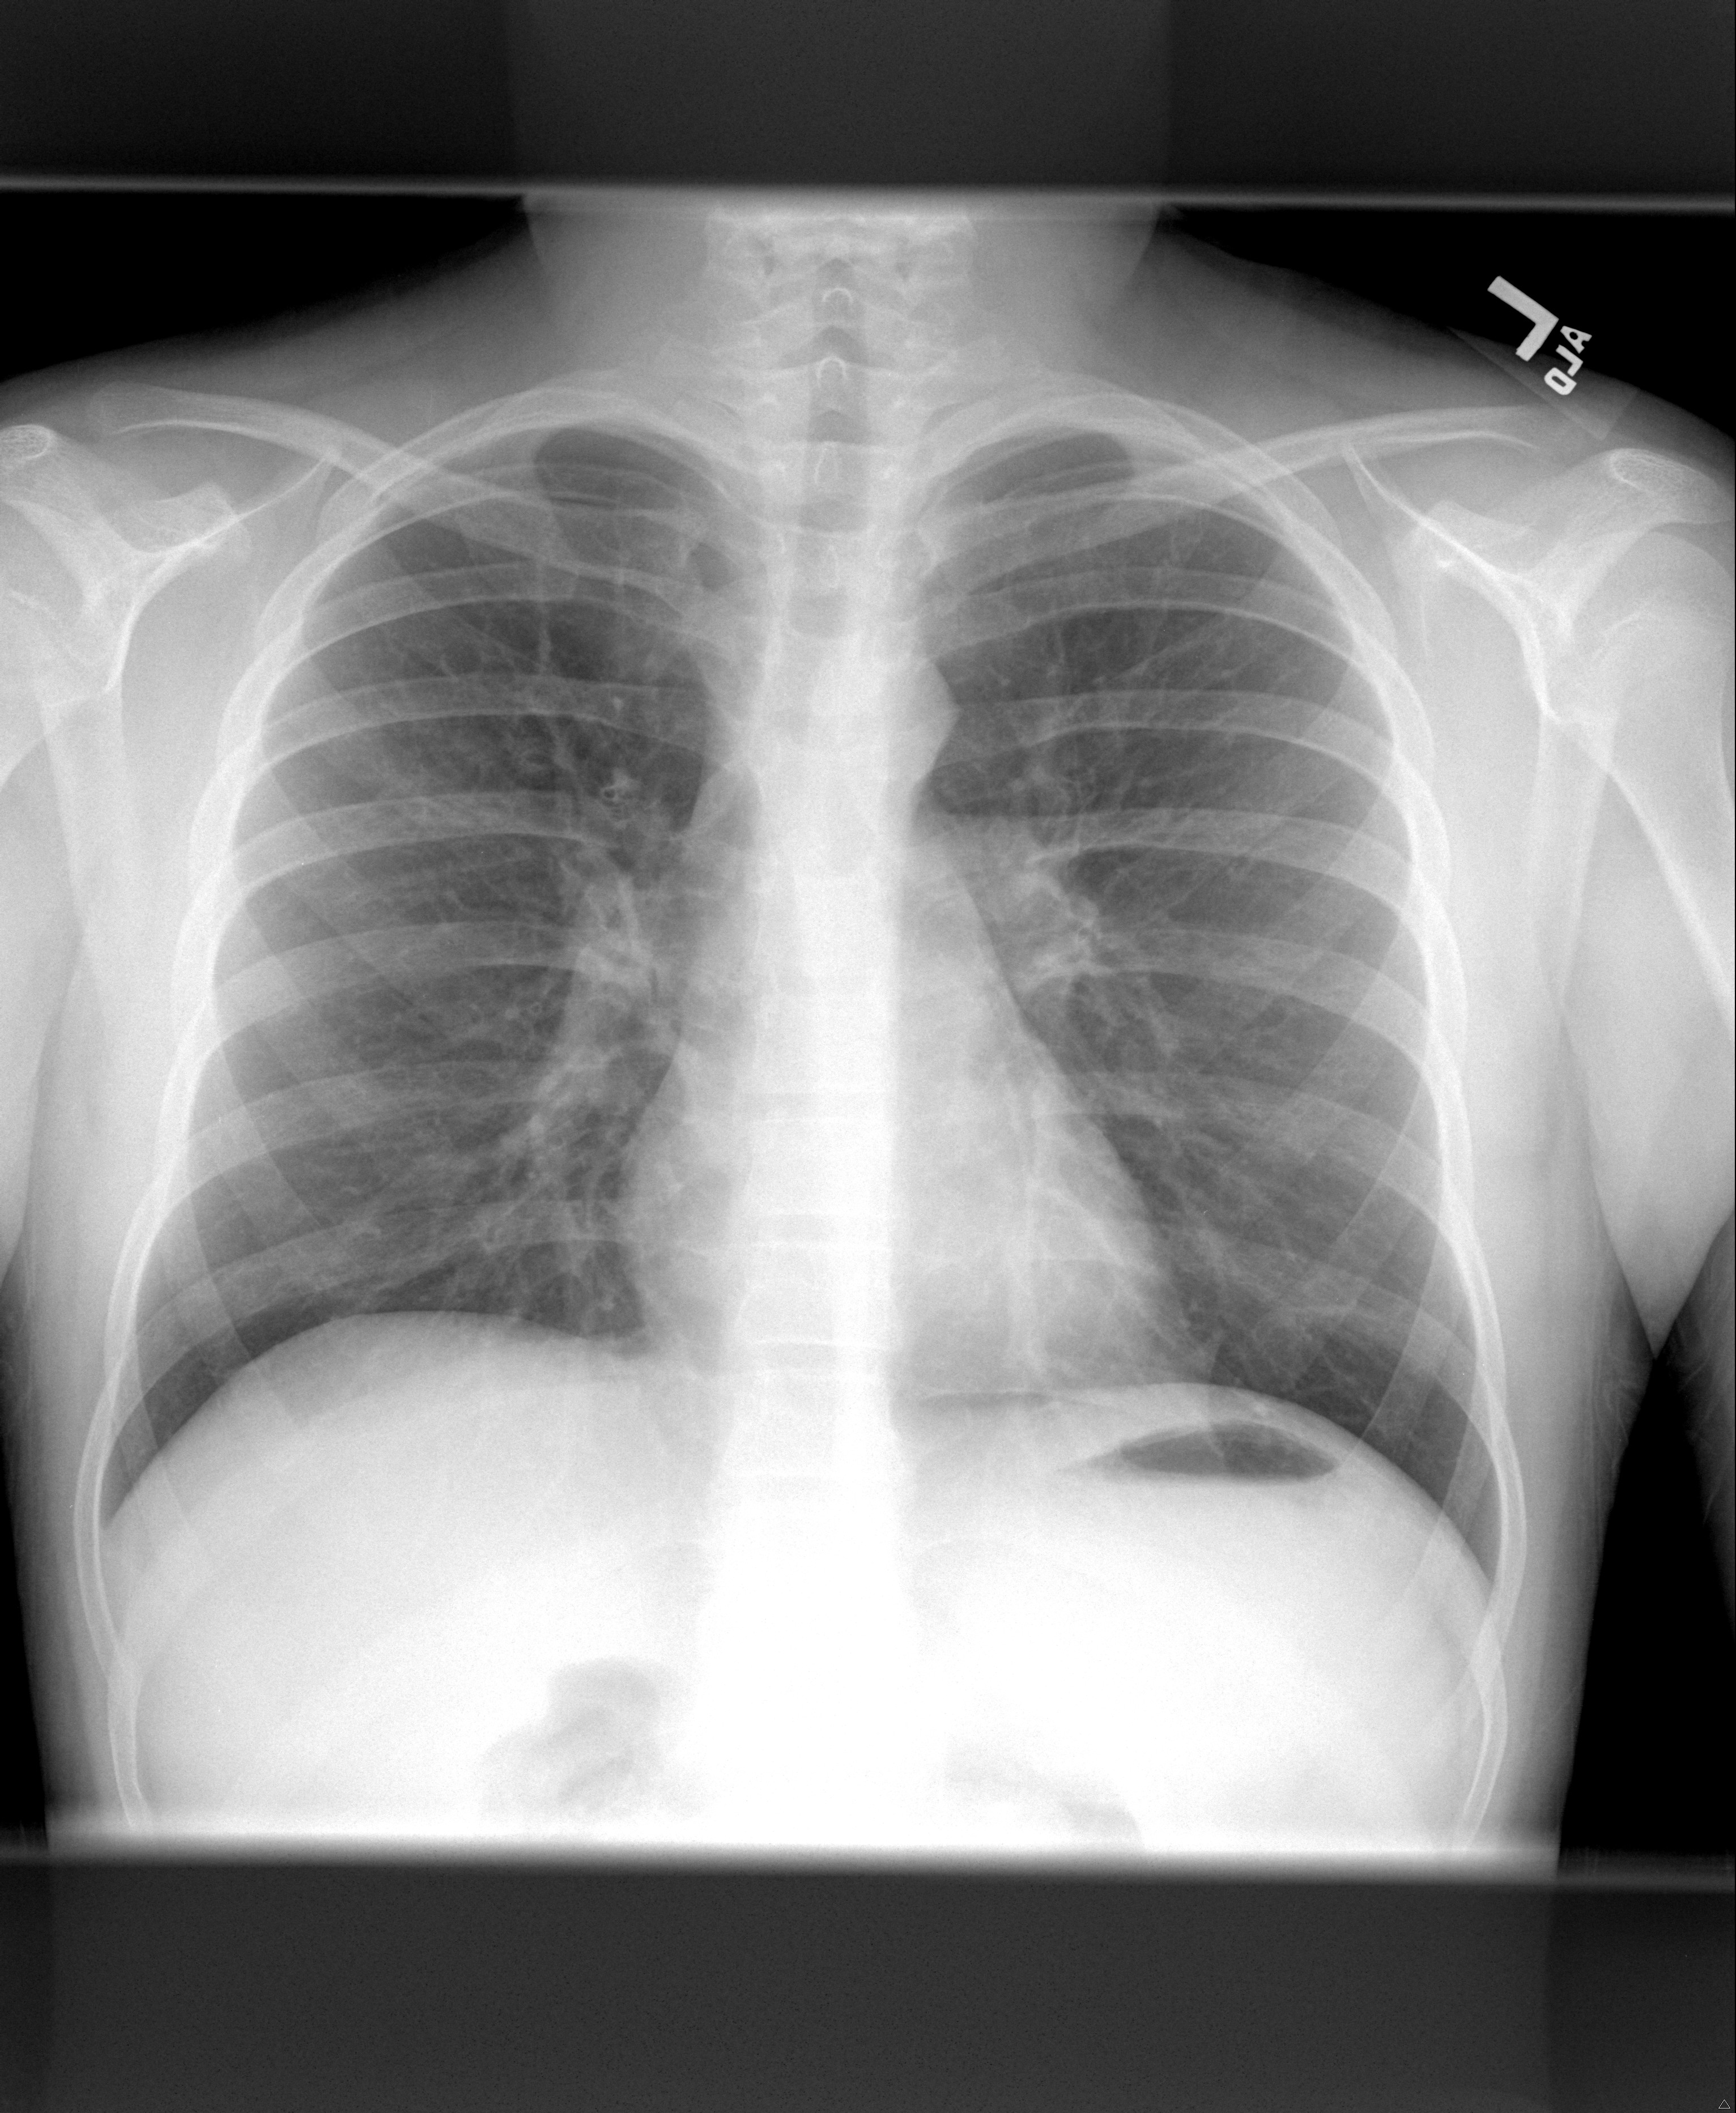

Key concepts in the management of severe asthma in children include verification of the correct diagnosis, evaluation of co-morbid diseases and assessment of compliance with controller medications. Establishing a treatment strategy based on combination therapy with proper medication delivery should be tailored to maximize patient and family adherence (1). In this case, the patient met diagnostic criteria for asthma based on symptoms and reversible airflow obstruction on pulmonary function testing.

Our patient had persistent asthma that was very poorly controlled. He initially was treated with a burst of oral corticosteroids for symptomatic relief. The inhaled corticosteroid component of his combination therapy was increased in strength, and a leukotriene inhibitor was added to his regimen. The patient and his family were counseled on the need for compliance with his daily controller medications. Extensive smoking cessation education was provided to the father. The patient returned in 2 months with improved, however still poorly controlled symptoms. Pulmonary function testing was significantly improved (FEV1 86% predicted). Regular nasal corticosteroids were added to help with allergic rhinitis. In addition, a proton pump inhibitor was added as an empiric trial of anti-reflux therapy.

Approximately 6 months later, the patient was still noticing substantial symptoms related to environmental allergen exposure. Pulmonary function testing continued to indicate mild obstructive disease. An IgE level was significantly elevated at 665 IU/ml (normal< 250 IU/ml). Formal allergy testing was obtained, and positive skin responses were found for several environmental aeroallergens. The patient was subsequently started on Omalizumab at standard dosing based on weight and baseline IgE level.